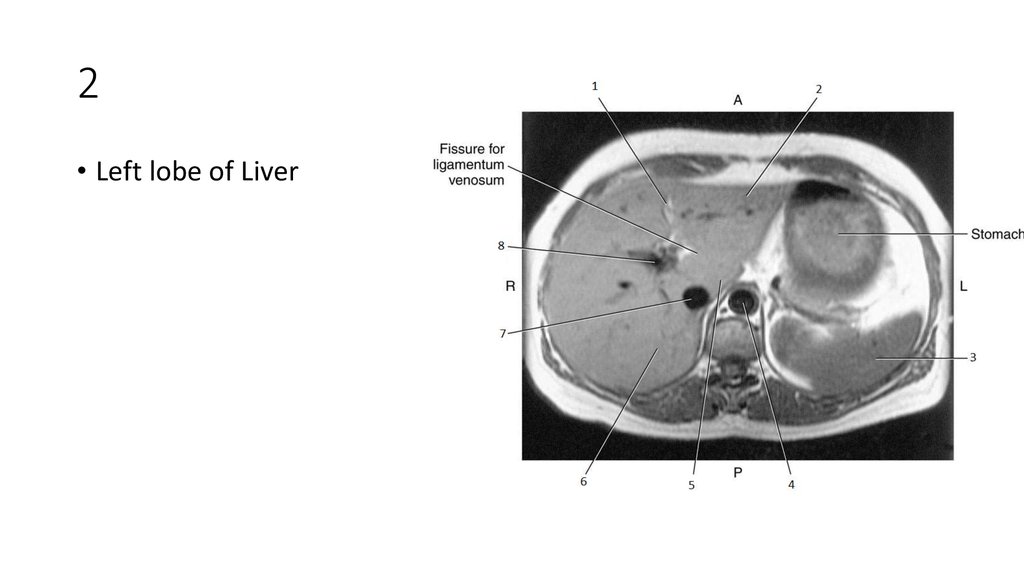

18. 2

19. 2

• Left lobe of Liver